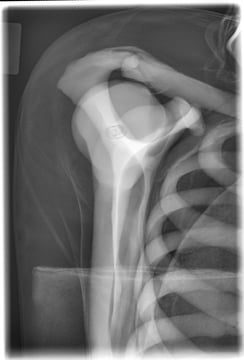

Bei der Y-Aufnahme ist der Unterschied sogar noch etwas deutlicher. Der gelbe Keil gibt deutlich mehr nach als der blaue ProFoam Wedge 45 ° Keil. Der ProFoam Wedge 45 ° Keil ist hart genug, um den Patienten in der richtigen Position zu halten und aus diesem Grund für diese Einstellung hervorragend geeignet. Die Bilder unten zeigen eine Y Aufnahme ap im Liegen - ein geeigneter "Plan B" wenn Patienten nicht stehen oder sitzen können.